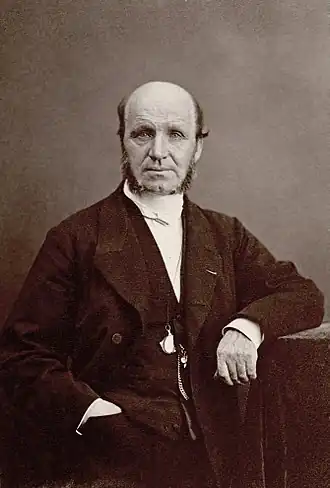

La maladie a été étudiée par Guillaume Duchenne de Boulogne dans les années 1850, qui pense que celle-ci n'est que musculaire. La première démonstration d'une atteinte de la moelle épinière est faite en 1853 par Cruveilhier au cours d'une autopsie, montrant une atrophie des racines antérieures. En 1860, Duchenne décrit cliniquement la forme bulbaire de la maladie et Jean-Martin Charcot démontre l'atteinte du bulbe dans ce cas. Ce dernier publie plusieurs cas d'atrophies musculaires et d'atteinte médullaire. En 1874, il présente ses conclusions dans ses douzième et treizième leçons, décrivant avec précision les symptômes et les lésions macroscopiques et microscopiques de la moelle[100].